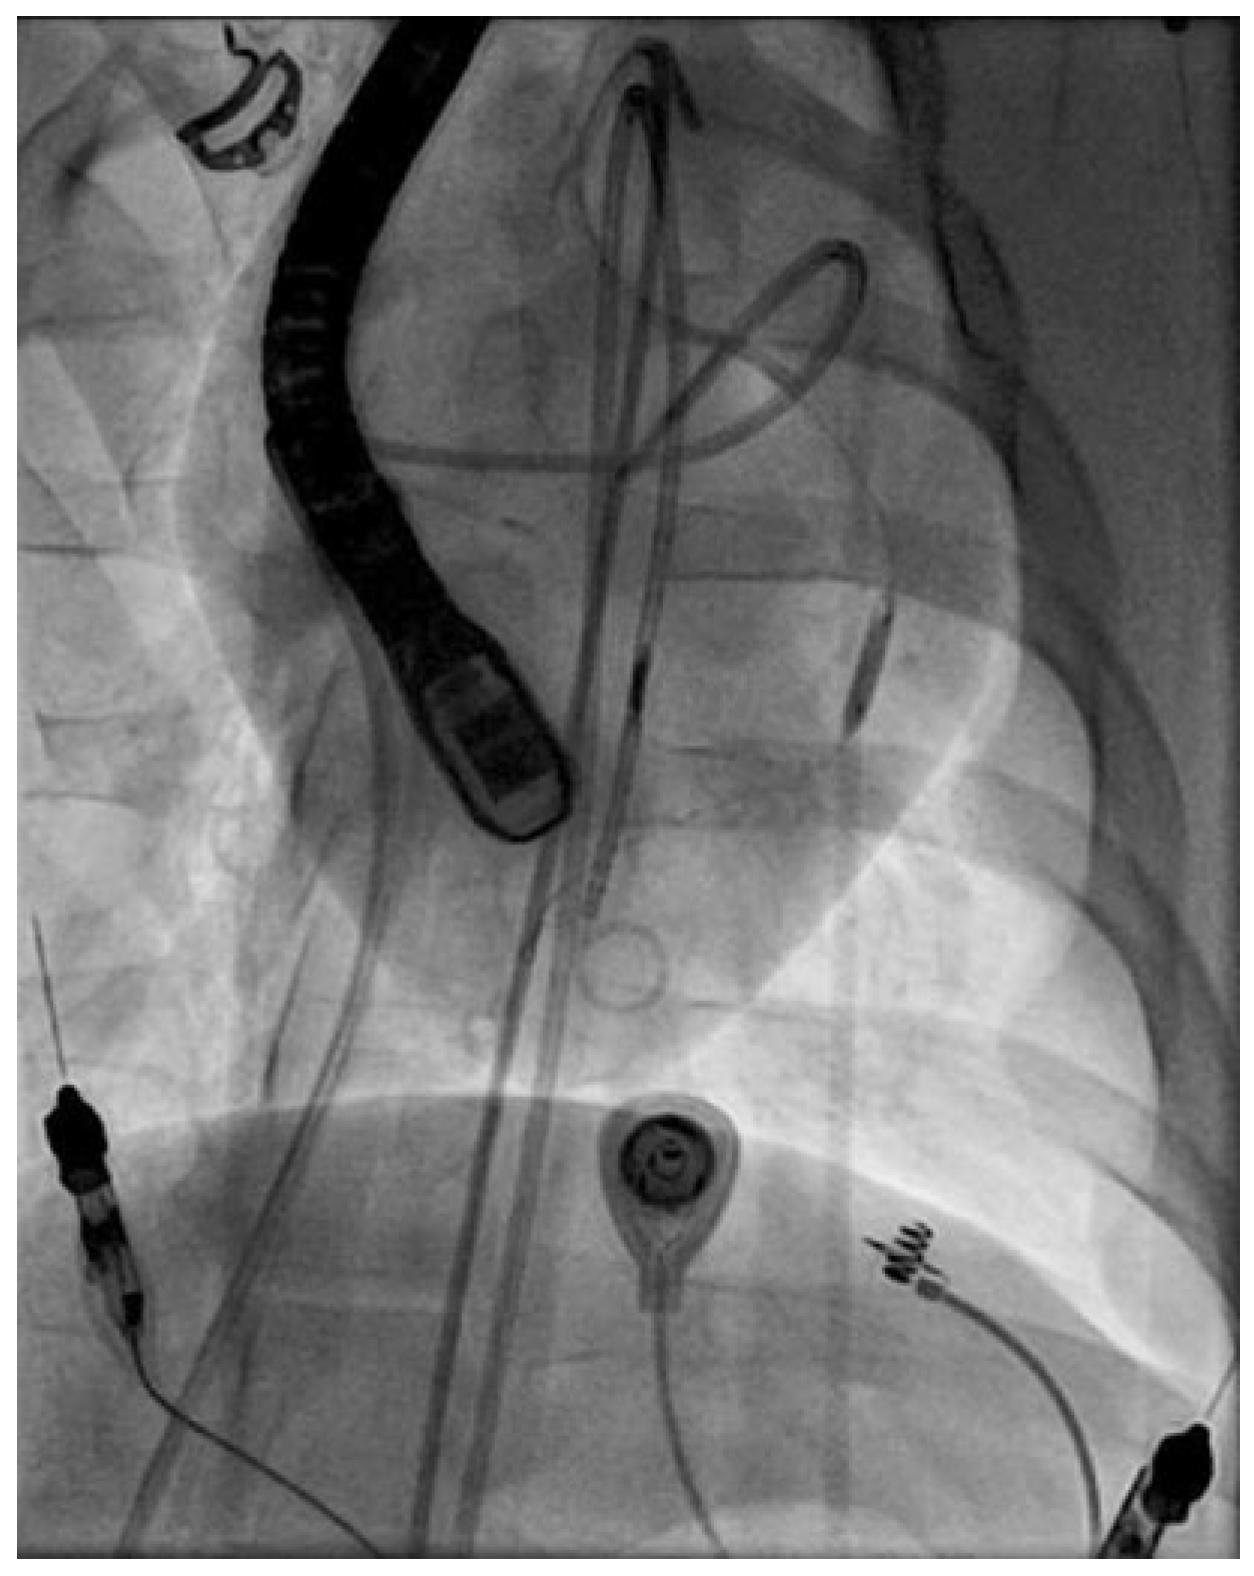

Introduction: Non invasive imaging studies (e.g. coronary computed tomography angiography (CCTA), coronary magnetic resonance angiography (CMRA)) are increasingly performed in several clinical contexts. Incidental finding of coronary anomalies is challenging. While coronary anomalies are the second most leading cause of sudden cardiac death in young athletes clinical relevance in asymptomatic patients is less clear. Cardiologists have to deal with the questions of clinical significance, prognosis, risk assessment and therapeutical options for patients with coronary anomalies.

Methods: A 42year old woman presented with typical chest pain after finishing a training run for a marathon at her family physician. As ECG showed negative T wave in lead III accompanied by increased cardiac troponin T- level (value = 351.6 ng/l; reference value <14 ng/l) she was referred for coronary angiography to our hospital.

Results: Coronary angiogram was presumptive for an anomolous origin of the right coronary artery (RCA) from the left coronary sinus. CCTA was performed showing an acute-angeled origin of the RCA from the opposite (= left) sinus with a proximal intramural course within the aortic wall. As cardiac ischemia due to exercise was present we estimated a high risk for cardiac death due to the coronary anomaly. Open heart surgery with reinsertion of the RCA at the right coronary sinus was perfomed. Fully recovery and restarting sportive activity was rapidly achieved after surgery.

Conclusions: The management of patients with incidental findings of coronary anomalies is challenging. Depending on the risk assessment for sudden cardiac death therapeutical options range from conservative treatment to more invasive procedures like angioplasty or open heart surgery. Surgical repair is the treatment of choice in symptomatic patients. In asymptomatic patients, especially in young and athletic adults, a positive stress test result should prompt to determine the most appropriate treatment option in a multidisciplinary heart team.